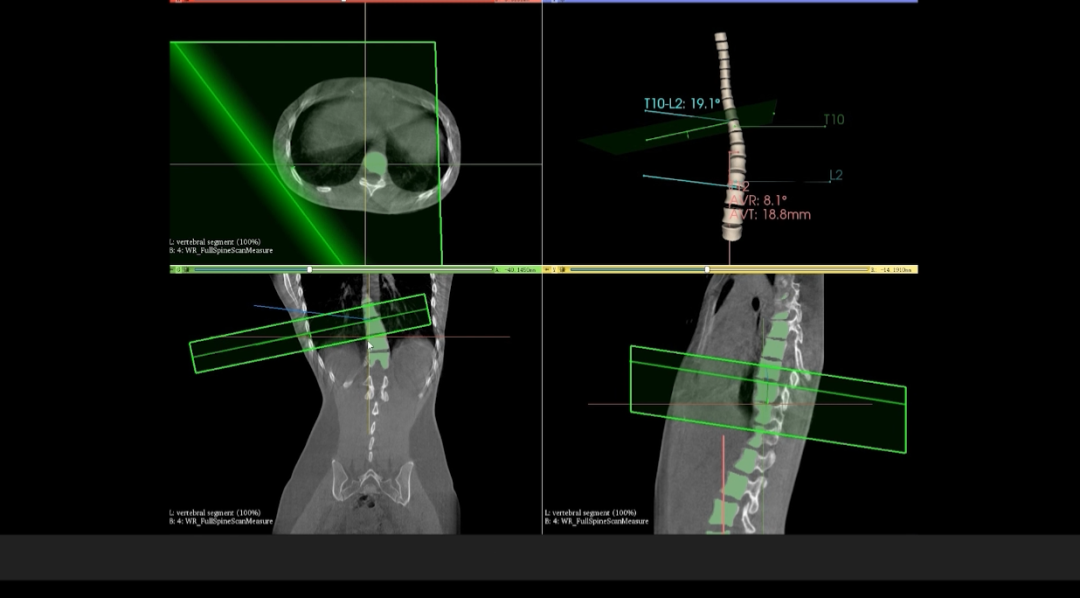

在與華西醫(yī)院開展的技術合作中,WR-3D的立位脊柱三維攝影技術能提供更加豐富的臨床信息,通過WR-3D的三維全脊柱掃描與重建,即可完成脊柱三維影像重建,無需進行角度拼接,消除二維Cobb角度測量的誤差,可以實現(xiàn)包括Cobb角、前/后凸角、椎體偏移/旋轉向量圖、椎體旋轉角條形圖、矢/冠狀面垂直軸偏距數(shù)據(jù)的自動測量;這項技術將為脊柱矯形的臨床診斷帶來從定性到定量的轉變,提供豐富的數(shù)據(jù)和圖表,為臨床尤其是手術方案的規(guī)劃制定提供非常精準的定量化數(shù)據(jù)支撐,不僅可以對脊柱冠狀面參數(shù)進行精準的定量評估,還可對矢狀面包括,頸椎前凸、后凸、腰椎前凸和后凸進行非常精準的評估。